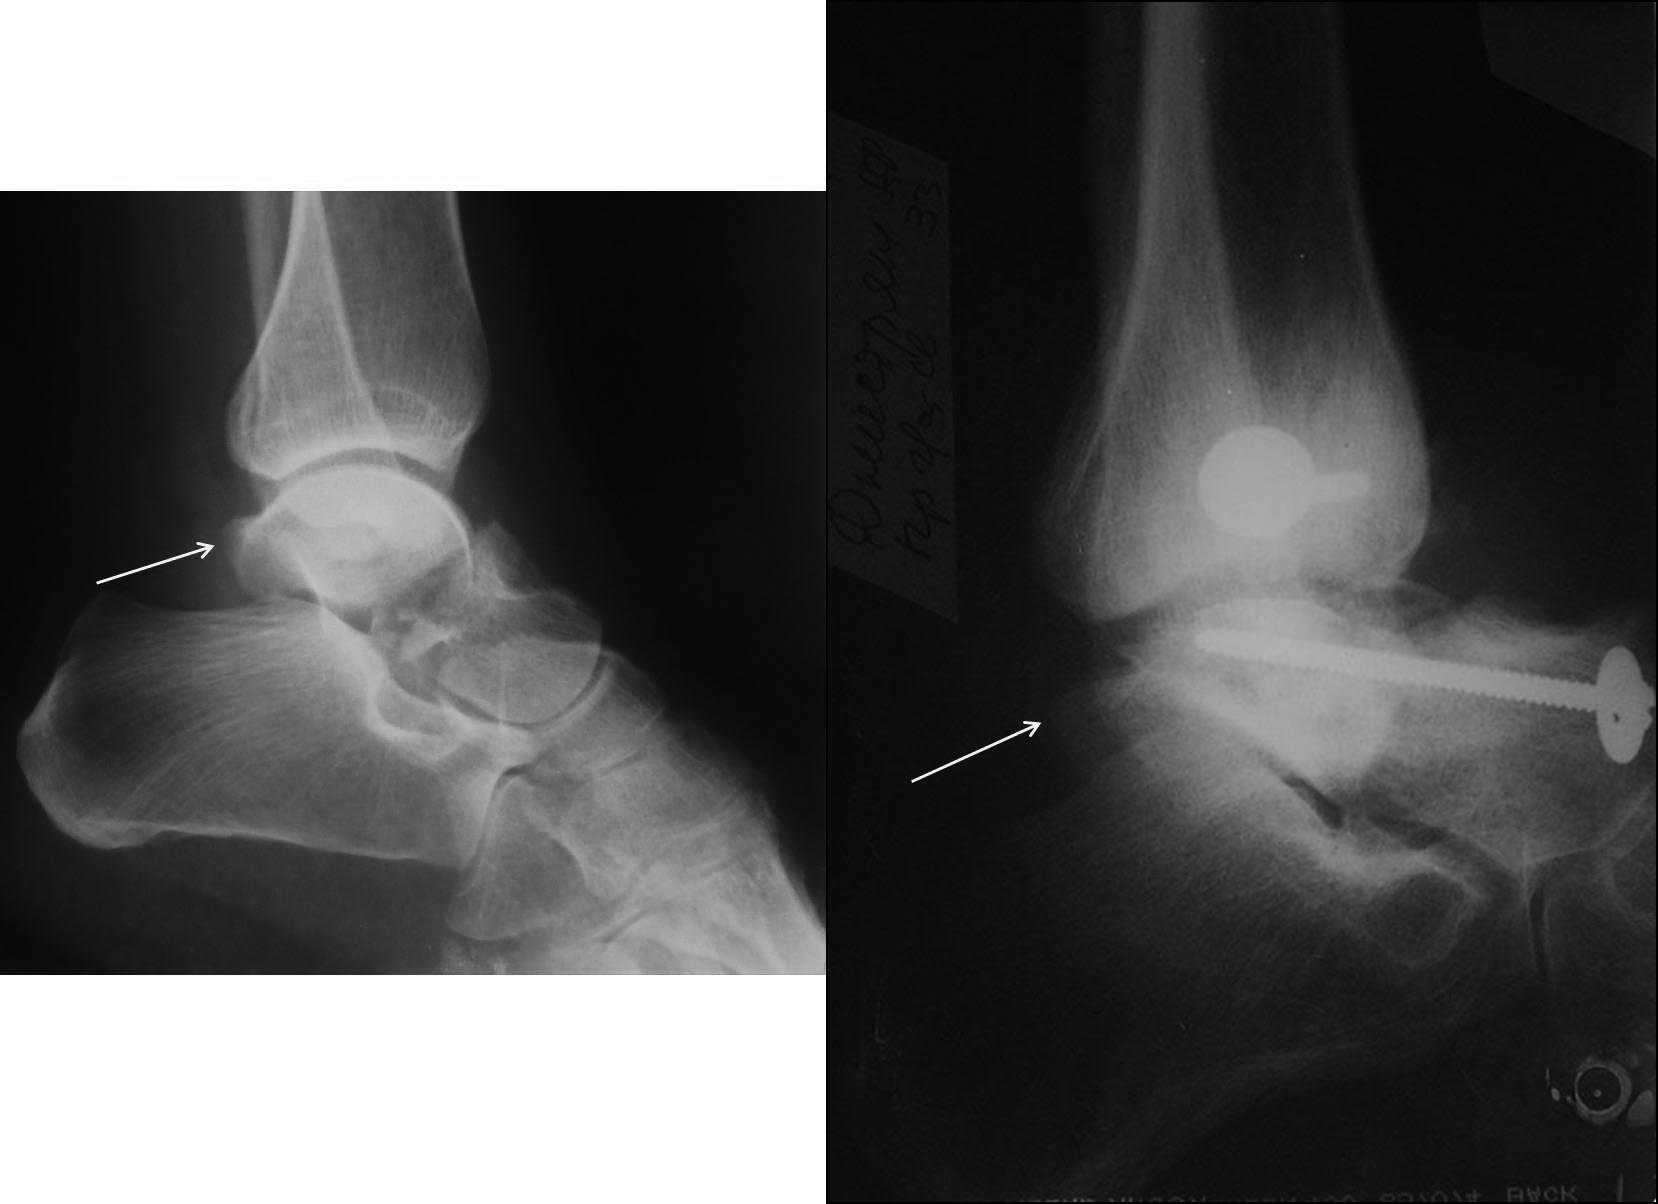

Вероятнее всего, речь изначально шла о не устраненном во время операции

вывихе проксимального фрагмента таранной кости. Во вложении похожий

случай, оперированный 10 дней назад (с послеоперационными снимками). Для

сравнения стрелками на двух рентгенограммах показан нависающий над

пяточной костью вывихнутый фрагмент таранной кости. На компьютерной

томограмме видно гораздо лучше. Так что о живом подтаранном суставе при

сохраняющемся подвывихе говорить не приходится. Кстати, остеотомия

внутренней лодыжки в такой ситуации - нормальный этап доступа, который

должен планироваться до операции, а не быть следствием "тяжелой

репозиции". Сейчас же, судя по плотности проксимального фрагмента, нужно

исключать асептический некроз таранной кости и ее несращение. От этого

будет зависеть тактика. Без КТ не обойтись. Во всяком случае, артродез

голеностопного сустава при несросшейся разрушающейся таранной кости

точно не будет правильным решением.